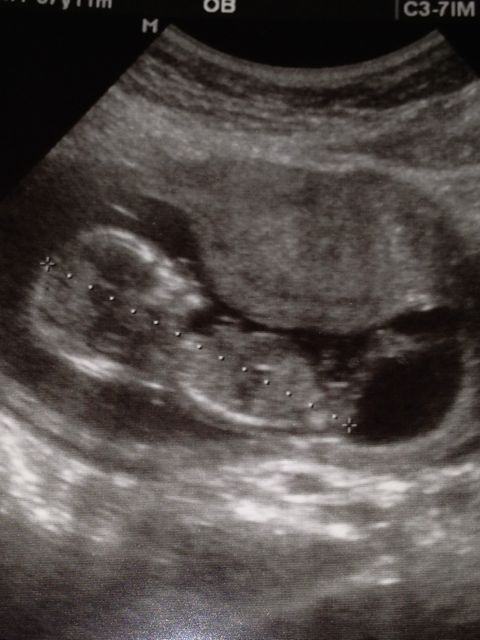

So here is my 13+4 week nub shot. Not sure if there is anything in here to guess off of but would appreciate any feedback!